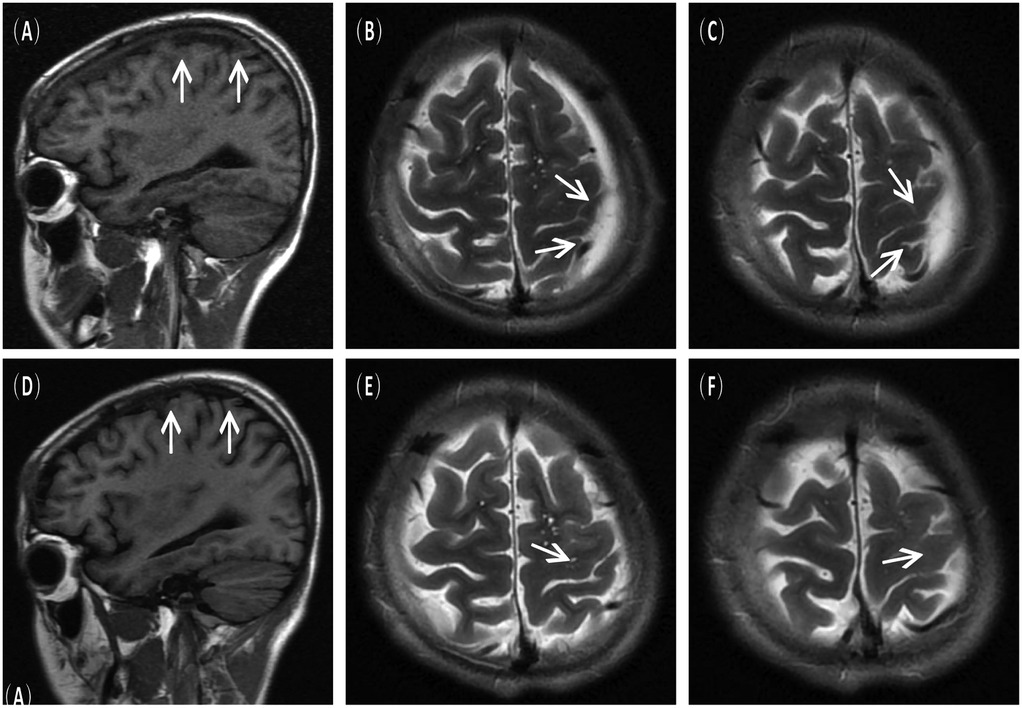

A 16-year-old male presented to the hospital with a 10-day history of episodic headache. Three years earlier, he had been evaluated for headache, and magnetic resonance imaging (MRI) identified an arachnoid cyst in the left fronto-temporo-parietal region (Figure 1). Given the absence of significant mass effect or neurological deficits and the resolution of symptoms, surgical intervention was not advised at that time. No specific intervention was performed, and the headache subsequently resolved on its own. No further imaging studies were conducted thereafter. Ten days ago, the patient experienced recurrent headaches without apparent cause or trigger, characterized by episodic attacks predominantly localized to the left occipital region. The headache was initially relieved by oral painkillers but reappeared 2 days before admission to the hospital, worsening compared to the previous episode. For further evaluation and management, the patient presented to our institution. An outpatient magnetic resonance imaging (MRI) revealed a massive chronic subdural hematoma (CSDH) in the left fronto-temporo-parietal region (Figure 2). No computed tomography angiography (CTA) or digital subtraction angiography (DSA) was performed at this time. The patient underwent burr-hole irrigation and drainage of the CSDH under general anaesthesia. Concurrently, the cyst wall was fenestrated to establish communication between the cyst and the extracerebral space. Postoperative imaging confirmed complete resolution of the hematoma and a significant reduction in the size of the cyst (Figures 3A–C). His headaches were relieved significantly compared with those of the previous day. The cyst did not recur on the patient's return visit 6 months after the operation (Figures 3D–F), and no symptoms such as headache were observed during the 6 months.

Figure 3. Postoperative imaging findings. (A–C) Immediate postoperative MRI scans showing resolution of the subdural hematoma and decreased size of the arachnoid cyst. (D–F) Follow–up MRI scans at 6 months post–surgery confirmed no recurrence of the cyst.